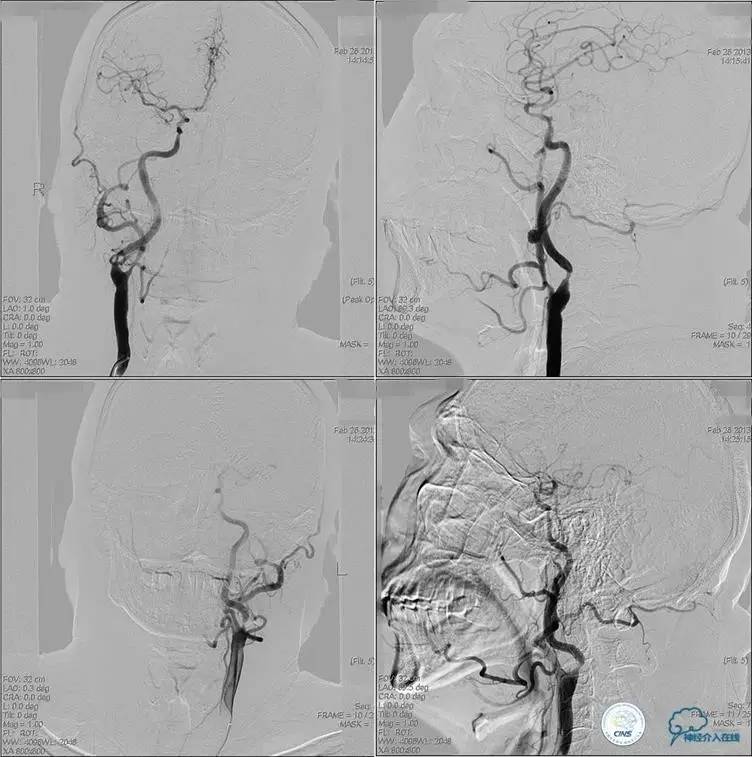

▼入院MR

神经内科保守治疗。

入院第三天,病情转差。

查体:构音障碍加重,右侧肢体肌力降落(近端Ⅱ级,远端0级)。

▼开通

出院情况:头晕症状消失,构音障碍缓解,进食无呛咳,饮水实验(-),右侧肢体远端肌力恢复到Ⅰ级。